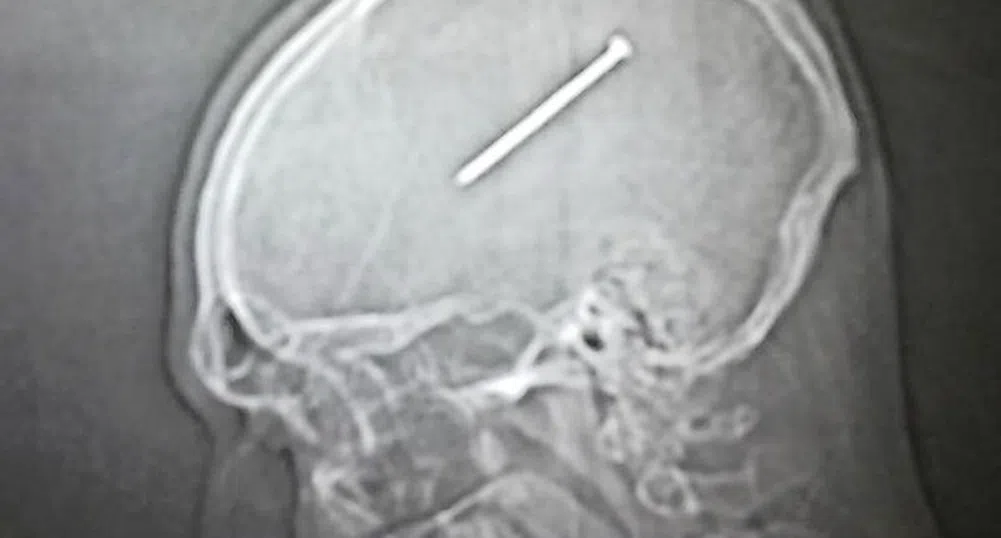

На следващия ден обаче усетил, че му се гади и съпругата му предложила да идат до болницата. След няколко часа била направена рентгенова снимка, на която се видяло, че пиронът се е забил в средата на мозъка му, на милиметри от мозъчния център, който контролира двигателните функции.